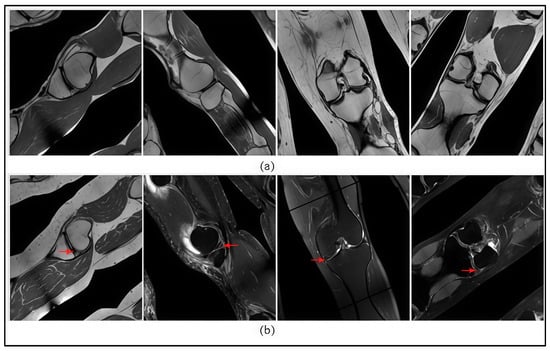

Spatial image augmentation was applied to enhance the generalization capability of the model and to address the limitations of the training dataset. Information-preserving techniques were used to maintain anatomical structures and contextual features, including Safe Rotate, ShiftScaleRotate, Random Sized BBox Safe Crop, and Perspective transformations.

A total of 500 images from each class were selected and augmented using the four aforementioned methods, resulting in a final dataset of 2000 images. Examples of the applied spatial transformations are presented in Figure 6.

Figure 6.

Augmentation results: (a) images without meniscus tear (class 0); (b) images with confirmed meniscus tear (class 1). Arrows indicate the site of the meniscus tear.